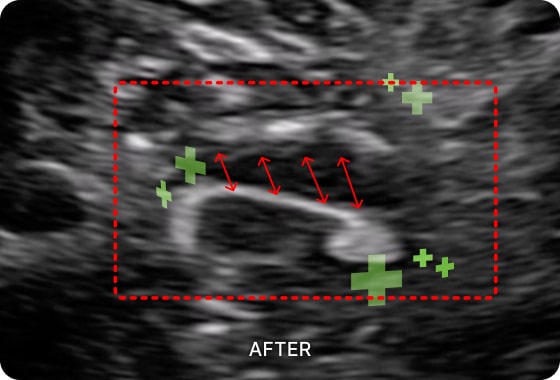

초음파 검사를 통해

디스크 통증의 직접적인

원인을 확인할 수 있습니다.

수핵이 돌출되면 면역 반응이 발생하는데 이 과정에서

염증성 사이토카인이라는 물질이 분비되어 주변 신경을

자극하고 심한 통증이나 저림을 유발합니다. 즉, 통증의 원인이 되는 신경유착을 초음파로 진단이 가능합니다.

손상된 조직을 복구하는 효과가 뛰어납니다. 초음파를 활용하여 신경을 압박하는

염증을 박리하고 손상된 조직을 재생합니다.